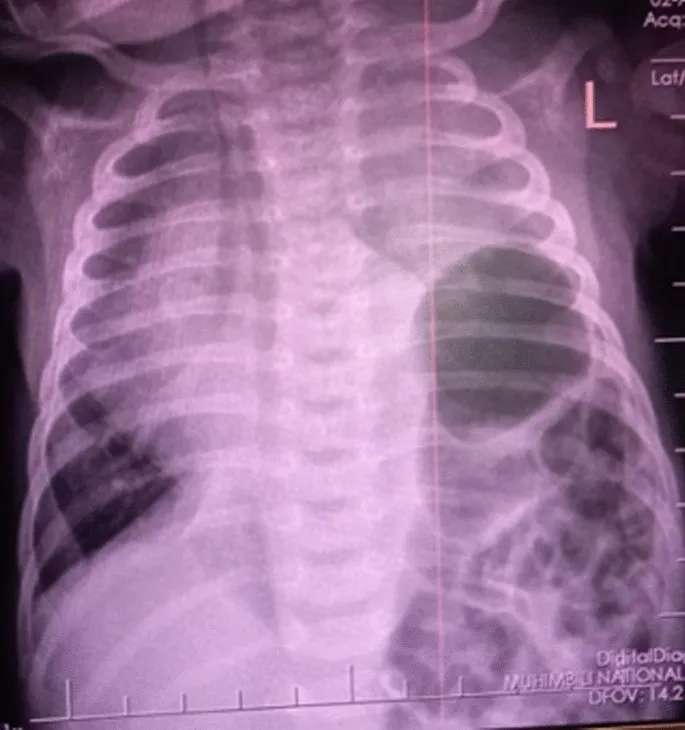

- CXR (Confirmatory): Bowel loops in chest, mediastinal shift, ↓ abdominal gas.

- Diagnosis: Chest X-ray (bowel in thorax, mediastinal shift); prenatal ultrasound for early detection.